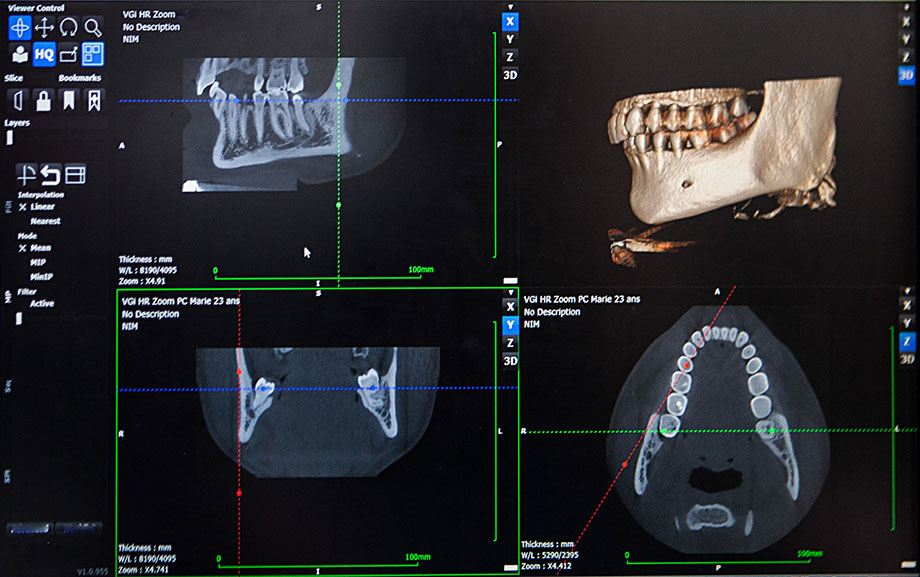

歯科用CTで正確で精度の高い診断

根管の形状は患者様ごと、歯1本ごとに異なります。そのため、歯科用CTにより患部を立体的に映し出し、根管の枝分かれや湾曲の状態を正確に把握した上で治療計画を立てます。的確な診査・診断は高精度の根管治療に欠かせません。